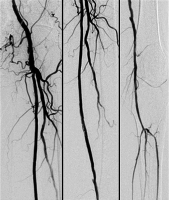

Reentry

Abbildung 2: Nach Passage mit dem Führungsdraht und Ballonkatheter.

Keywords:

Angiogramm

,

Arteria femoralis

Gefäßmedizin